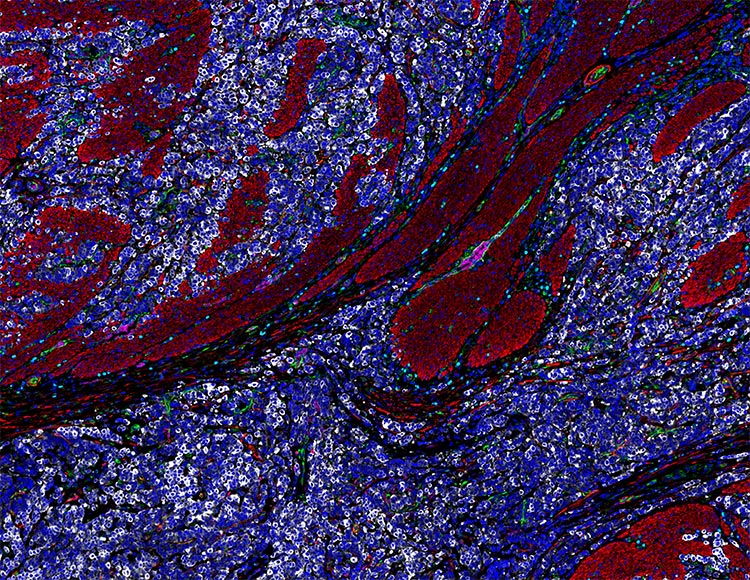

Orion 14 plex imaging of human low-grade glioma. Image courtesy of Scott M. Palisoul, Madhumala K. Sadanandappa, and George J. Zanazzi, Dartmouth Hitchcock Medical Center.